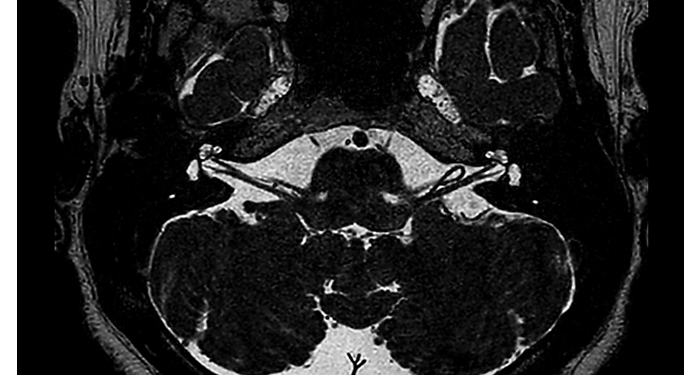

70% of radiologists consider neuro indications to be challenging, mostly due to a lack of appropriate imaging and visualization techniques¹. Philips aims to provide the best possible diagnostic clarity and treatment guidance for all patients with neurological disorders. By leveraging our dStream digital platform, this year, we are introducing, a set of novel imaging and visualization strategies. These may empower you to resolve complex neuro questions with more certainty, as well as unlock new neuro territories in advanced Neurofunctional applications. This is a key step towards elevating neuro diagnostics and ultimately touching more lives with MR imaging. ¹ TMTG Market Survey 2016

New neuro applications

Take a look at our other neuro applications